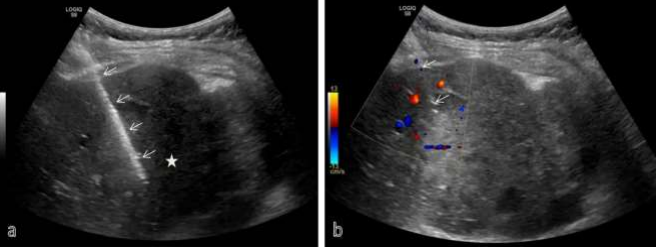

Figure 03: USG guided biopsy has been performed from the right lobe liver lesion in this suspected case of carcinoma gall bladder with liver metastasis. Almost entire needle (arrows) is seen in a with its tip in liver lesion (asterisk). Color doppler image shows vessels (in red and blue colors) on either sides of needle (arrow) which is carefully inserted avoiding the vessels.

Figure 04: 69 Y / Male, operated case of carcinoma colon, on observation. Surveillance CT scan shows an irregular hypodense lesion in right lobe of liver (black arrow in a) and associated focal IHBR dilatation (yellow arrow in a). Correlative ultrasound shows an irregular hyperechoic lesion in right lobe of liver (black arrow in b). USG guided FNAC was done (c) with needle close to the branch of portal vein (white arrow in c) and is avoided.